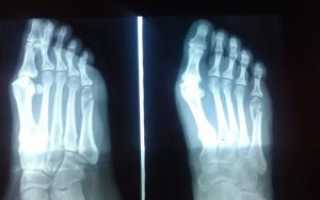

При любом переломе, а особенно 5-й плюсневой кости, осуществляется рентгенография стопы в 3-х проекциях: боковая, переднезадняя и косая.

В тяжелых случаях возможно применение других методов лучевой диагностики: МРТ или метод функциональной визуализации.

После перелома основания 5 плюсневой кости поставить диагноз можно по наличию травмы, жалобам пациента, визуальному осмотру стопы, а также с использованием рентгенологического оборудования.

Перед визитом к врачу вам будет выполнена контрольная рентгенография. С этими снимками вас осмотрит ваш лечащий врач и у вас будет возможность сравнить рентгенограммы до и после операции. Признаки сращения обычно становятся видны не раньше, чем через 6-8 недель после операции.